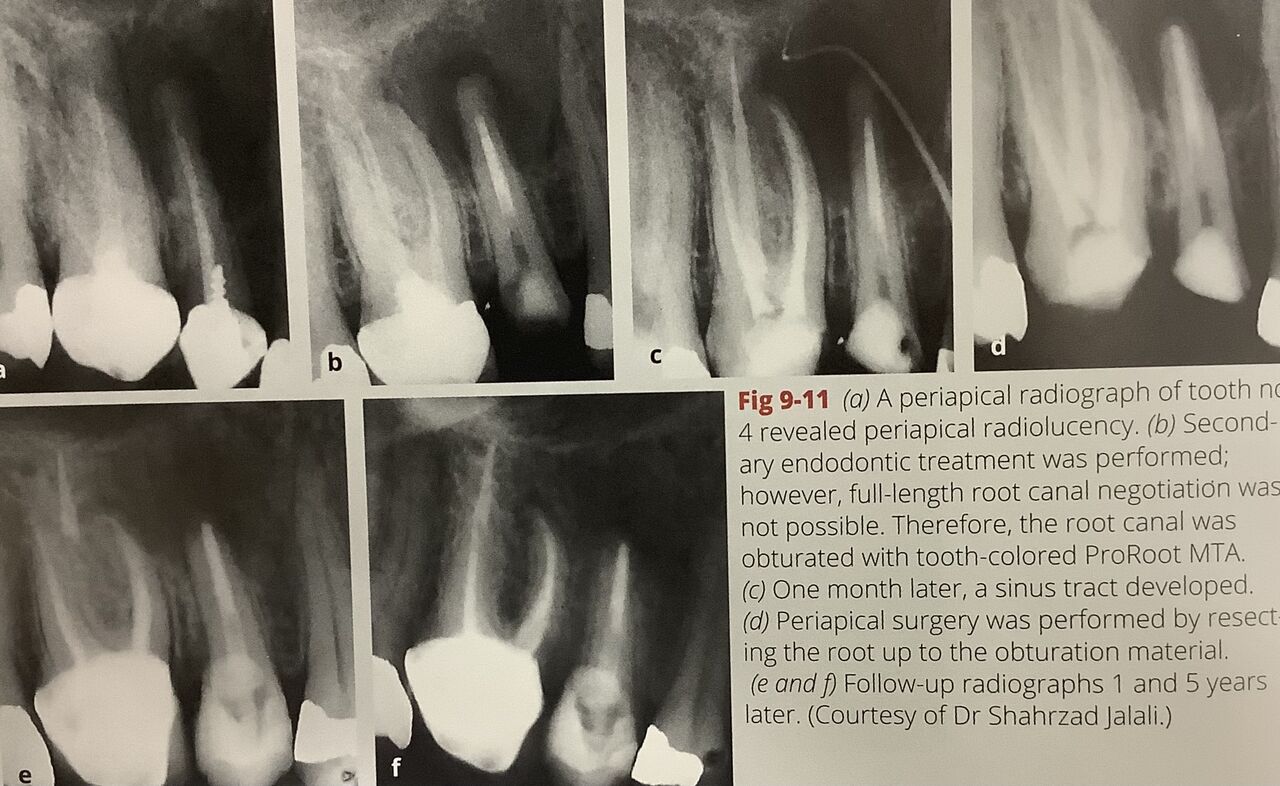

左から

差し歯の根っこに大きな影があります。

再治療をこころみましたが、先っぽまで開きません。

1ヶ月後、残念ながら膿が出てきました。

そこに白く写るポイントを差し込んで撮ったのが、

右真ん中のレントゲンです。

根っこの所から膿が出ていると確認できました。

で、外科治療で根っこの先を前に詰めていた位置まで削りとりました。

下が1年後、5年後です。

黒い影が小さくなって、白く見える骨が出来てきています。